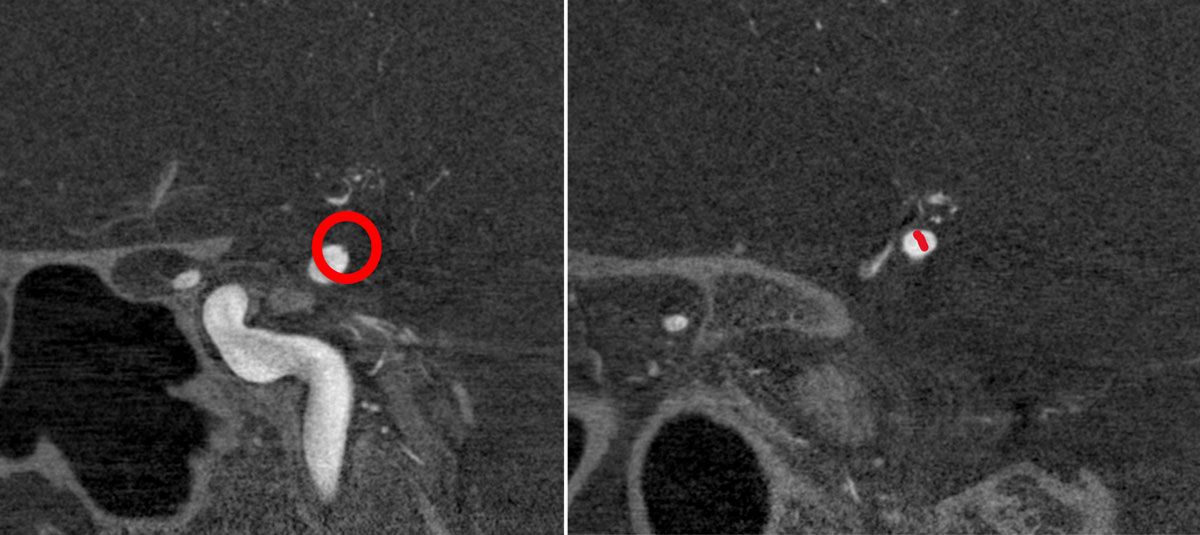

VASO-CT post